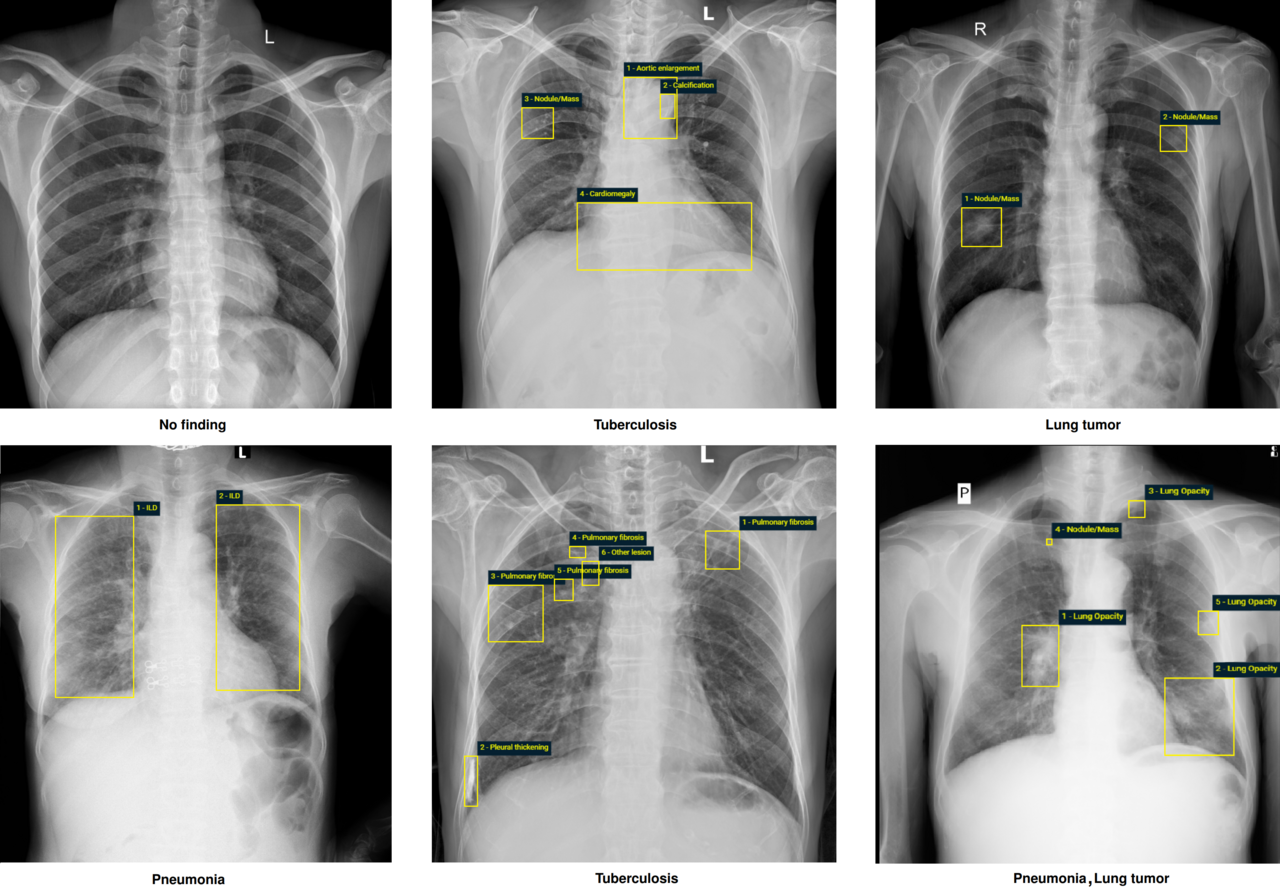

Examples of CXRs with radiologist’s annotations. Abnormal findings (local labels) marked by radiologists are plotted on the original images for visualization purposes. The global labels are in bold and listed at the bottom of each example.

The dataset contains more than 100,000 chest X-ray scans that were retrospectively collected from two major hospitals in Vietnam. Out of this raw data, we released 18,000 images that were manually annotated by a total of 17 experienced radiologists with 22 local labels of rectangles surrounding abnormalities and 6 global labels of suspected diseases. The released dataset is divided into a training set of 15,000 and a test set of 3,000. Each scan in the training set was independently labeled by 3 radiologists, while each scan in the test set was labeled by the consensus of 5 radiologists. All images are in DICOM format and the labels from training and test sets are made publicly available.